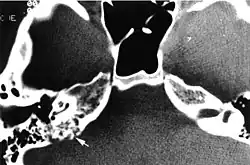

Imaging studies help to identify the tumor and the specific anatomic site of involvement. Magnetic resonance images show a hyperintensity (hypervascularity) of a heterogeneous mass by T1 weighted images. Computed tomography shows a multilocular, lytic destructive temporal bone mass, centered on the vestibular aqueduct (between internal auditory canal and sigmoid sinus).[1][6][7]